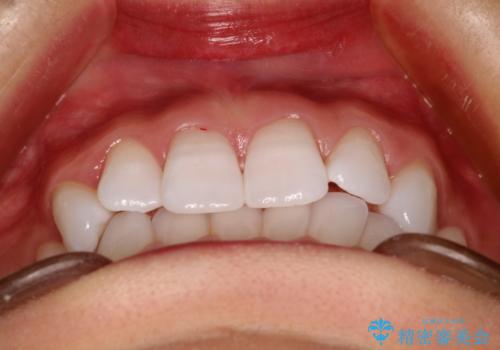

- 前歯の傾きと、ガタガタが気になるとのことで来院されました。

アスリートの方でしたので、競技に支障が少ないインビザラインで治療することとなりました。

前歯の傾きや高さをシミュレーションで患者様と確認しながら、歯並びを仕上げていきました。